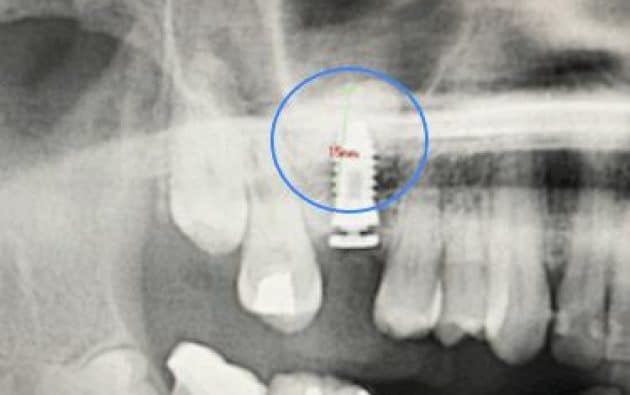

Antes y después de una elevación de seno maxilar

En estas imágenes puedes ver el antes y después de una elevación de seno maxilar realizada en nuestra clínica.

En la primera radiografía se observa la falta de hueso en la zona posterior del maxilar superior. En la segunda imagen, ya regenerada, se aprecia el implante dental correctamente integrado.